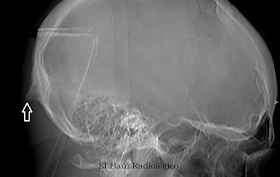

FIGURA  6) En la radiografía lateral del cráneo se aprecian con nitidez el espolón calcareo que se ha formado a partir de la protuberancia occipital .

FIGURA 1) El espolón occipital en una radiografía lateral de cráneo.